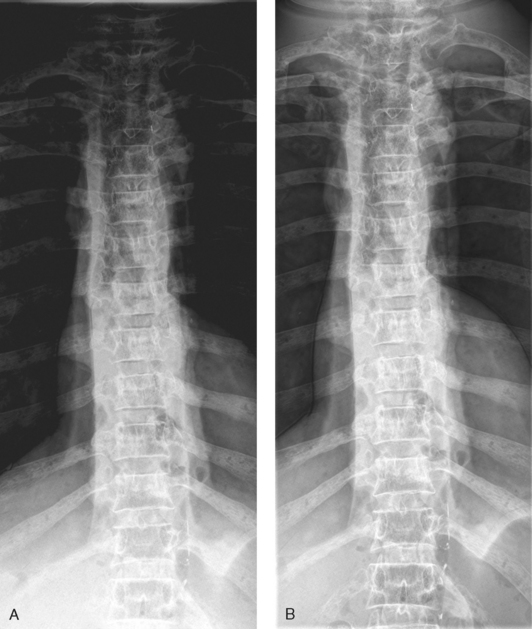

• The wedge filter is used for areas of the body where tissue density varies gradually from one end to the other along the long axis of the body. The wedge filter can be used to improve image quality of AP projections of the thoracic spine (Fig. 2-6).

Fig. 2-6 A, AP projection of thoracic spine without compensating filter. B, Same projection with Ferlic wedge filter. Note more even density of spine, and all vertebrae are shown.

• The trough filter is best used for areas of the body where the subject density in the center is much greater than at the edges. This filter has been successfully applied to improving PA projections of the chest (Fig. 2-7).

Fig. 2-7 A, AP projection of chest without compensating filter. B, Same projection with Supertech trough filter. Lower lung fields and mediastinum are better shown.